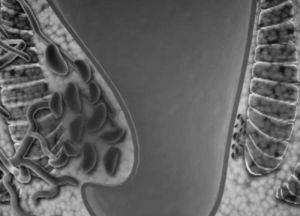

Це неинфекционное захворювання, але воно характеризується запальним процесом, в результаті якого спостерігається збільшення вен патологічного характеру. Перша ознака - поява шишок або гемороїдальних вузлів.

Шишки можуть утворюватися різних розмірів і знаходяться вони навколо товстої кишки.

При цій формі геморою свічки не призначають, тільки при внутрішній. До складу мазей обов'язково входять гормони, що запобігають утворенню тромбів.